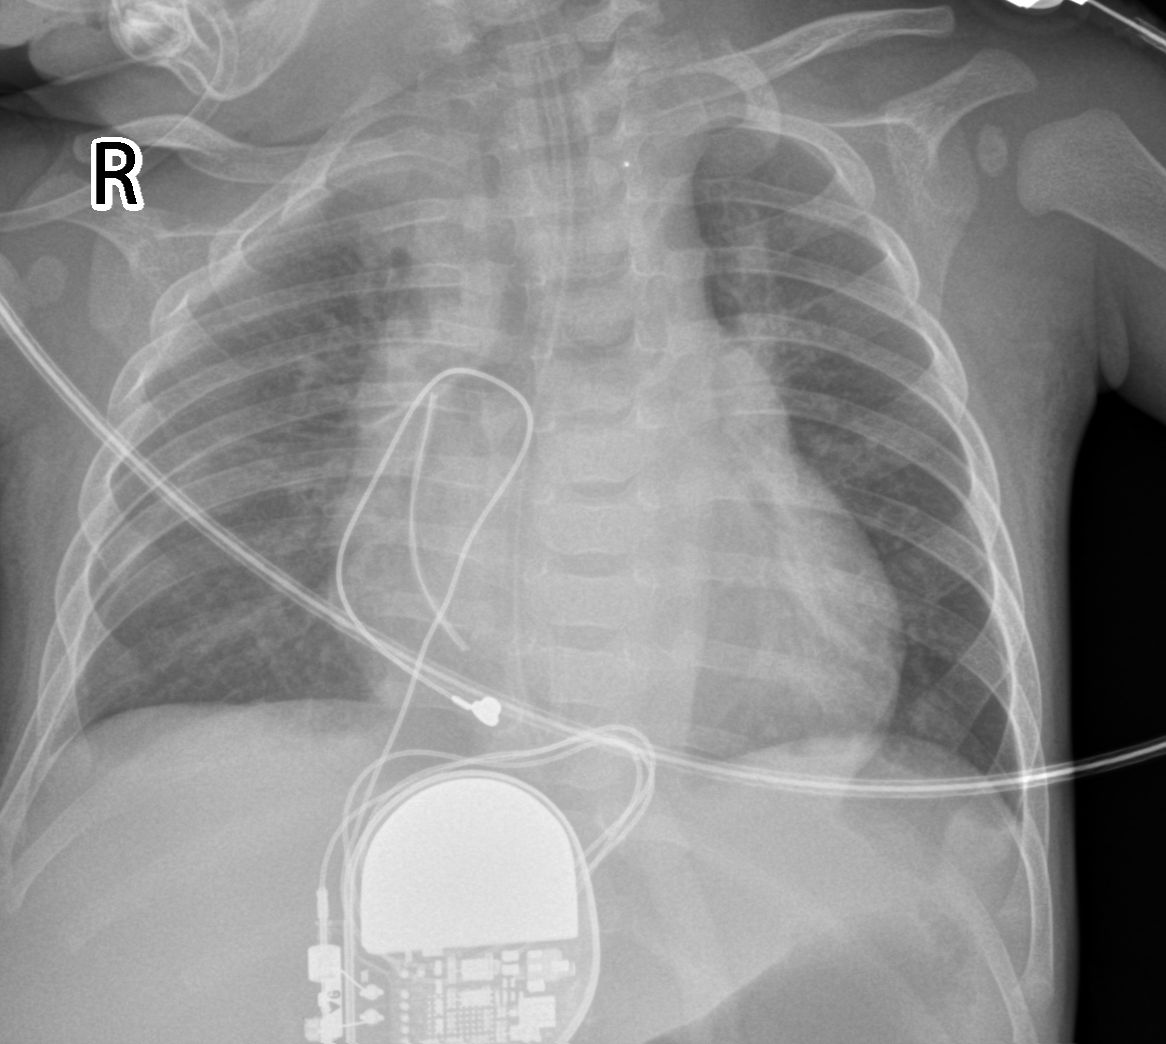

急诊手术开始了,打开心包,修补心脏,根据心外膜电极的特点,测试选择最佳的起搏位点。把像纽扣一样的起搏电极头端牢牢缝在了心脏表面,术中操作如同行走于钢丝。当电极与起搏器连接后,看着可可心脏有力而规律地复跳,手术医生黄鹏教授、邓喜成教授终于舒了口气。接着心脏起搏器被植入在了孩子的上腹部皮下,术中仔细地程控了心外膜电极的参数与阈值,调整起搏器的参数。可可顺利结束了手术,送入CICU心脏监护团队进行严密监护,目前病情稳定,已转入普通病房。

这是一例以抢救生命为目的的急诊手术,也是省内首例小儿心外膜起搏器植入术。小婴儿通过心外膜心脏起搏治疗,可以维持心脏节律,提供孩子足够的生长空间,保护外周血管,为后期心内膜起搏导线植入留有充分的空间。湖南省儿童医院心脏中心内外科的协同治疗,对于低年龄、低体重、危重复杂心脏病救治,有着得天独厚的的优势。未来必将在先天性心脏病、复杂心律失常的综合救治上,开拓新的领域。